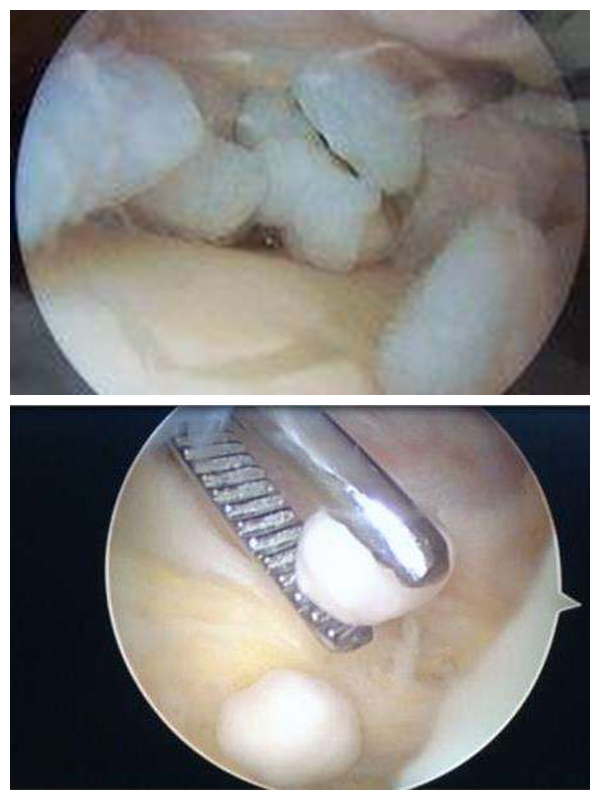

关节镜下逮`老鼠

【骨科】"关节鼠"作祟多年,关节镜一举"除害"助健康!